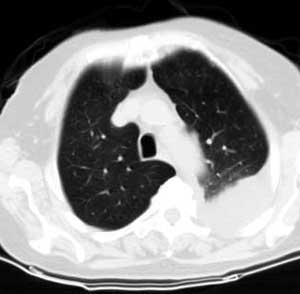

测ct值3-6hu,

既然ct值是3-6hu,还不如考虑包裹性积液。

支持包裹性胸腔积液。

请上传纵隔窗。目前还是支技包裹性积液(明显梭形),即使是间皮瘤并积液也少梭形的。

从图片看,包裹性积液好象更合理,梭形,ct值3-5hu(在哪看到的?);胸膜间皮瘤如此规则,不多见。

左侧背部胸膜肥厚,伴包裹性积液,不考虑间皮瘤.